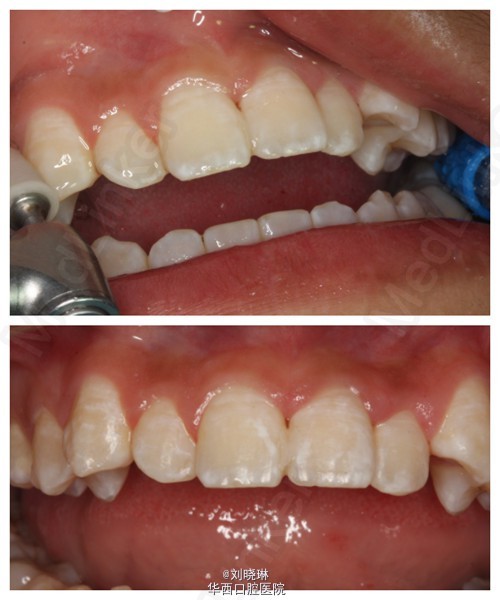

病人14岁,外伤导致上前牙脱落,患牙离体时间超过30小时。给患者讲明离体时间过长,患牙又未做正确方式保存,再植成功率低,患者要求试保留再植,术前签知情同意书。